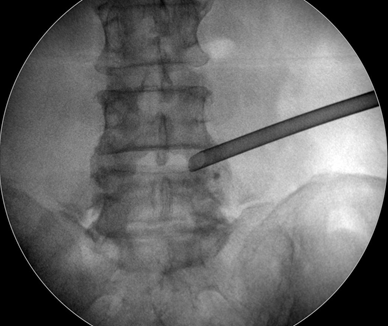

椎間孔鏡微創(chuàng)手術(shù)全程在影像導(dǎo)航引導(dǎo)下進(jìn)行,定位精確;針孔將突出髓核消融和取出,達(dá)到與開放性手術(shù)同樣的目的;不再大動(dòng)干戈、傷筋動(dòng)骨。杜醫(yī)師介紹,該微創(chuàng)療法,手術(shù)目標(biāo)性強(qiáng)、不融合間隙、手術(shù)部位的創(chuàng)傷小、恢復(fù)快、相關(guān)并發(fā)癥少,術(shù)后病患即可下地活動(dòng),相對(duì)減輕了專職護(hù)理人員和家屬的術(shù)后護(hù)理壓力和負(fù)擔(dān)。